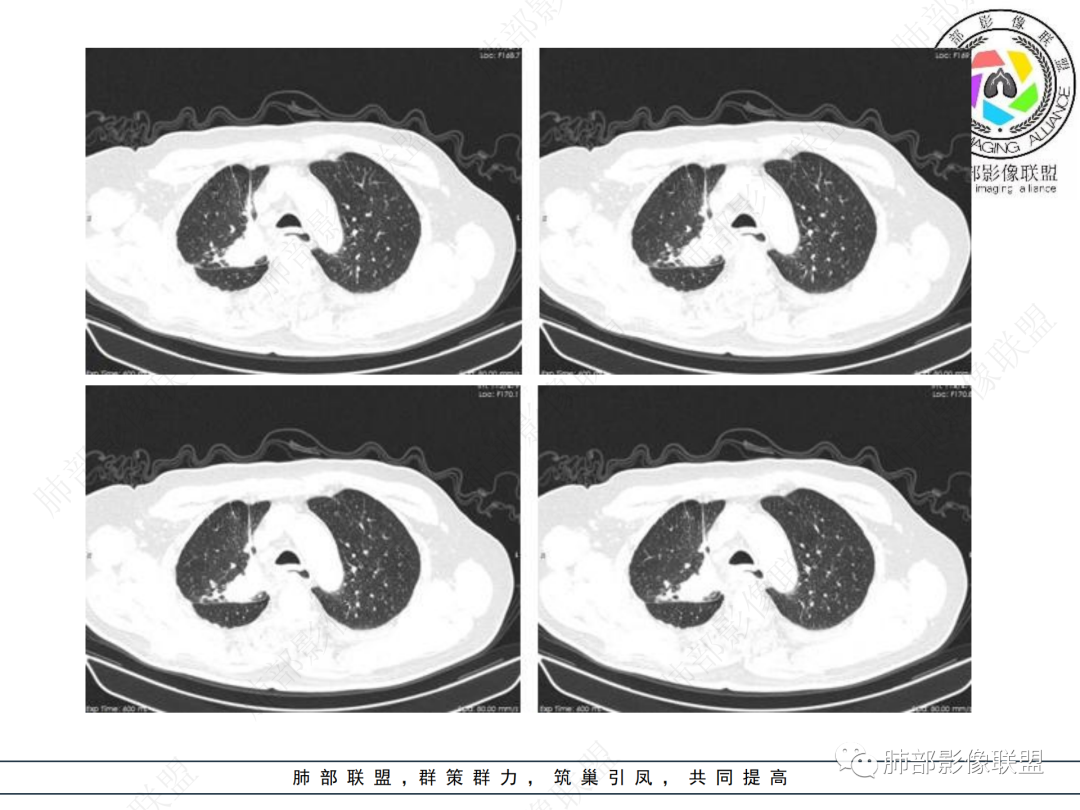

右肺上叶可见一团块影,边界清,有膨隆有凹陷,边缘可见毛刺,斜裂可见牵拉,不均匀强化,内可见液化,临近支气管未见明确阻塞,考虑腺癌可能,鉴别脓肿,结核等

右肺上叶团块,边缘毛糙,长索条,周围斑点影,邻近胸膜增厚,不均匀强化,其内小低密度灶边界清,考虑炎性肉芽肿,腺癌待排

男性,69岁 反复咳嗽2年余,加重3天入院。CT示右肺上叶尖段不规则实变影,周边伴条索影,支气管未见明显堵塞,增强不均匀强化,考虑为恶性,腺癌可能

男,69,反复咳嗽2年,加重3天入院,右肺上叶软组织密度肿块影,边界尚清晰,边缘见毛刺及胸膜牵拉,右肺上叶支气管壁增厚,增强扫描不均匀性强化,考虑腺癌可能,鉴别炎性病变。

右肺上叶见不规则团块,边缘清晰,周围可见长索条及斑片影,胸膜顶增厚,右侧斜裂部分增厚,右上肺体积略缩小,增强后不均匀强化,考虑炎性肉芽肿性病变,结核?鉴别腺癌

右侧胸廓变小,右肺上叶团块,边缘毛糙,长索条,周围斑点影,邻近胸膜增厚,气管不规整,密度不均,不均匀强化,考虑炎性肉芽肿,腺癌待排。